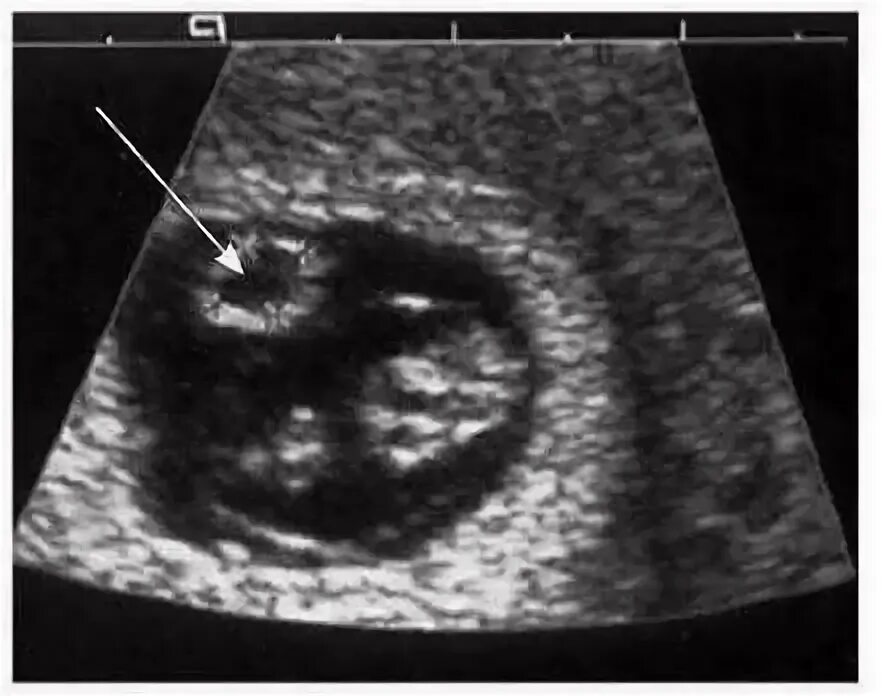

Плодное яйцо желточный мешочек